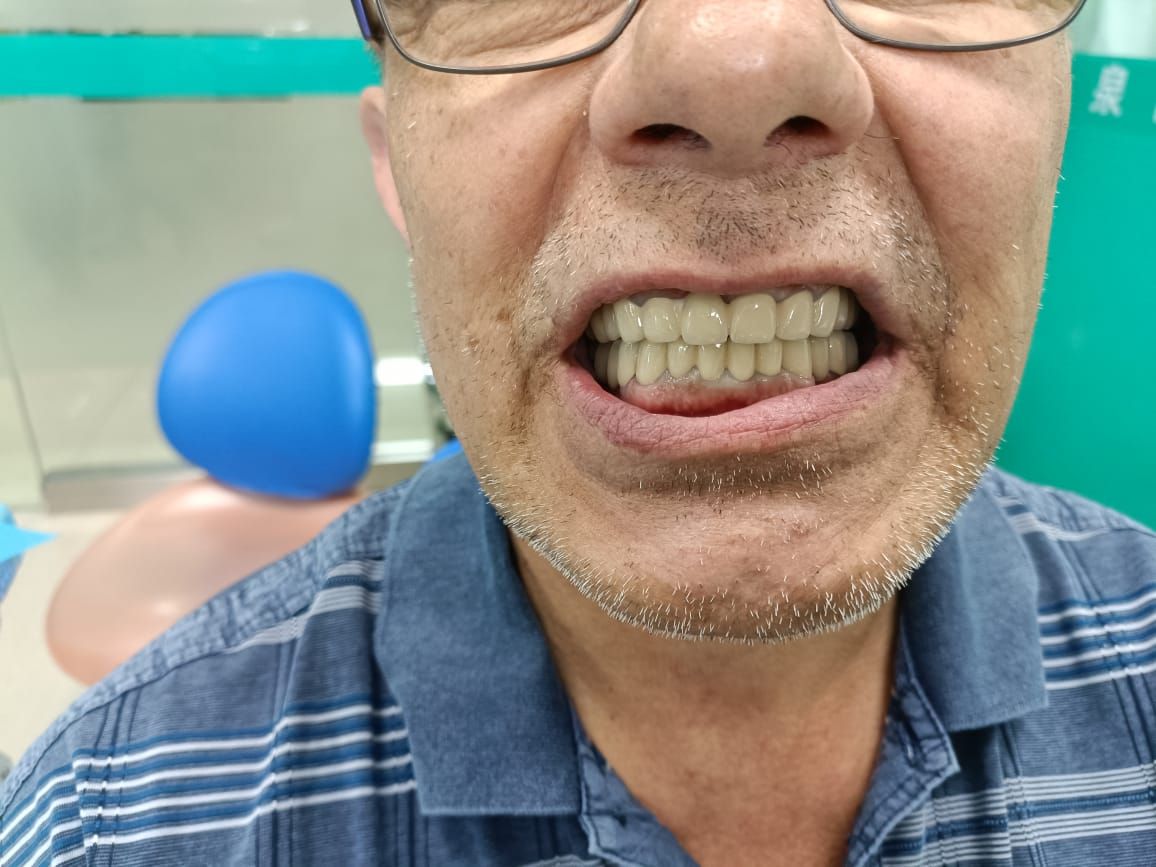

Первая городская больница г. Хэйхэ — это стоматология, завоевавшая прекрасную репутацию среди российских пациентов. Лечение проводят лучшие врачи с многолетним стажем, приглашенные из Пекина, Харбина и других городов Китая. Лечение зубов в нашей больнице это качественное обслуживание, низкие цены и бесплатное проживание в гостинице для всех пациентов в течении процедуры лечения зубов.

Наша больница располагает современным оборудованием, позволяющим проводить точную диагностику и эффективное лечение, а также восстанавливать целостность зубного ряда. Большой опыт сотрудников, индивидуальный подход к клиентам и превосходное владение инновационными методиками – все это входит в стандарт оказания медицинских услуг, и мы его строго придерживаемся.

Запишитесь на консультацию по телефонам +7(914)619-51-67, либо через форму обратной связи на сайте. Мы вернем вам красивую улыбку.